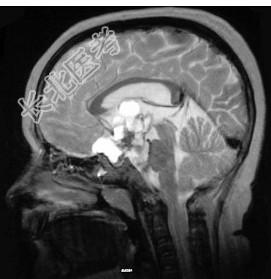

- 单项选择题关于颅咽管瘤(见图)以下哪项不正确 ( )

A、占原发性颅内肿瘤的2%~5%

B、多见于成年人

C、囊性变且包膜钙化多见

D、主要被分为成釉细胞型和鳞状乳头型

E、常发生在鞍上